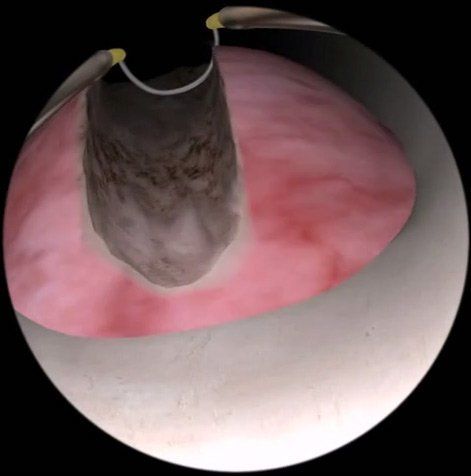

அறுவை சிகிச்சை